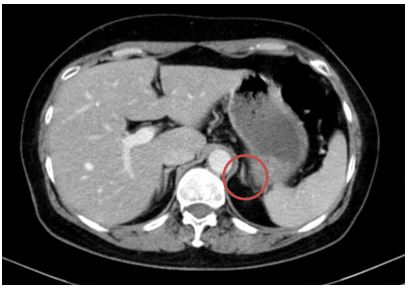

-  Chụp cắt lớp vi tính bụng: Theo dõi dày khu trú tuyến thượng thận trái tạo nốt đường kính khoảng 9mm

Hình 3. Hình ảnh chụp CT bụng trước điều trị: Nốt tuyến thượng thận trái